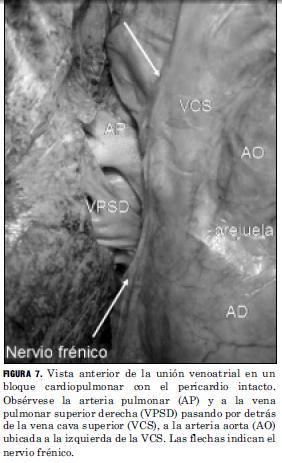

El nodo sinusal se logró identificar bajo magnificación óptica 10X en 17 de 32 casos estudiados (53,12%) y se ubicó 6 de 17 (35,29%) en la pared de la VCS, 8 de 17 (47,05%) sobre la unión venoatrial y 3 de 17 (17,64%) en la pared de la AD. En todos los casos se encontró en los cuadrantes posteriores, en 13 casos (76,47%) sobre el posteroderecho y en 4 casos (23,53%) sobre el posteroizquierdo (Figura 7).

Los resultados de nuestro estudio ponen de manifiesto que la presencia de MC atrial en la VCS es un hecho constante, presente en todos los casos analizados, localizados en el espacio periadventicial de la VCS, con una altura que varió entre 15 y 56 mm. El patrón de distribución fue fenestrado y discontinuo en la gran mayoría de los casos, y su dirección oblicua ascendente / descendente. Las entradas de MC se localizaron mayoritariamente en sus cuadrantes anteriores, en número de 2 a 4, con presencia constante de un contingente de fibras musculares que proviene de la orejuela derecha. Otro contingente importante proviene de la cara lateral de la AD penetrando la VCS en su sector lateral derecho, y se encuentra en relación cercana con el nervio frénico derecho y el nodo sinusal. La identificación del nodo sinusal se puede ver limitada en los cadáveres más jóvenes y en los que no presentan infiltración grasa en el sector epicárdico del mismo (12, 13).